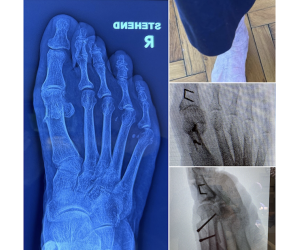

Correcting MIS Lapidus

Dr. Kris Di Nucci

MIS surgeons — here is a patient who presents 10 months after an MIS Lapidus arthrodesis. She reports recurrence of her bunion and mild sesamoid...